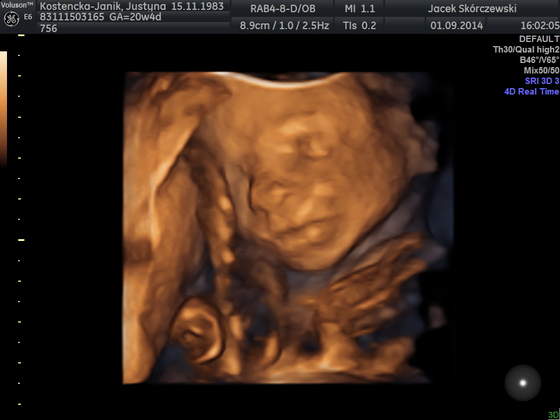

a to buźka (wg mnie podobny do mnie)

IMG_20140901_1_22.jpgIMG_20140901_1_23.jpg